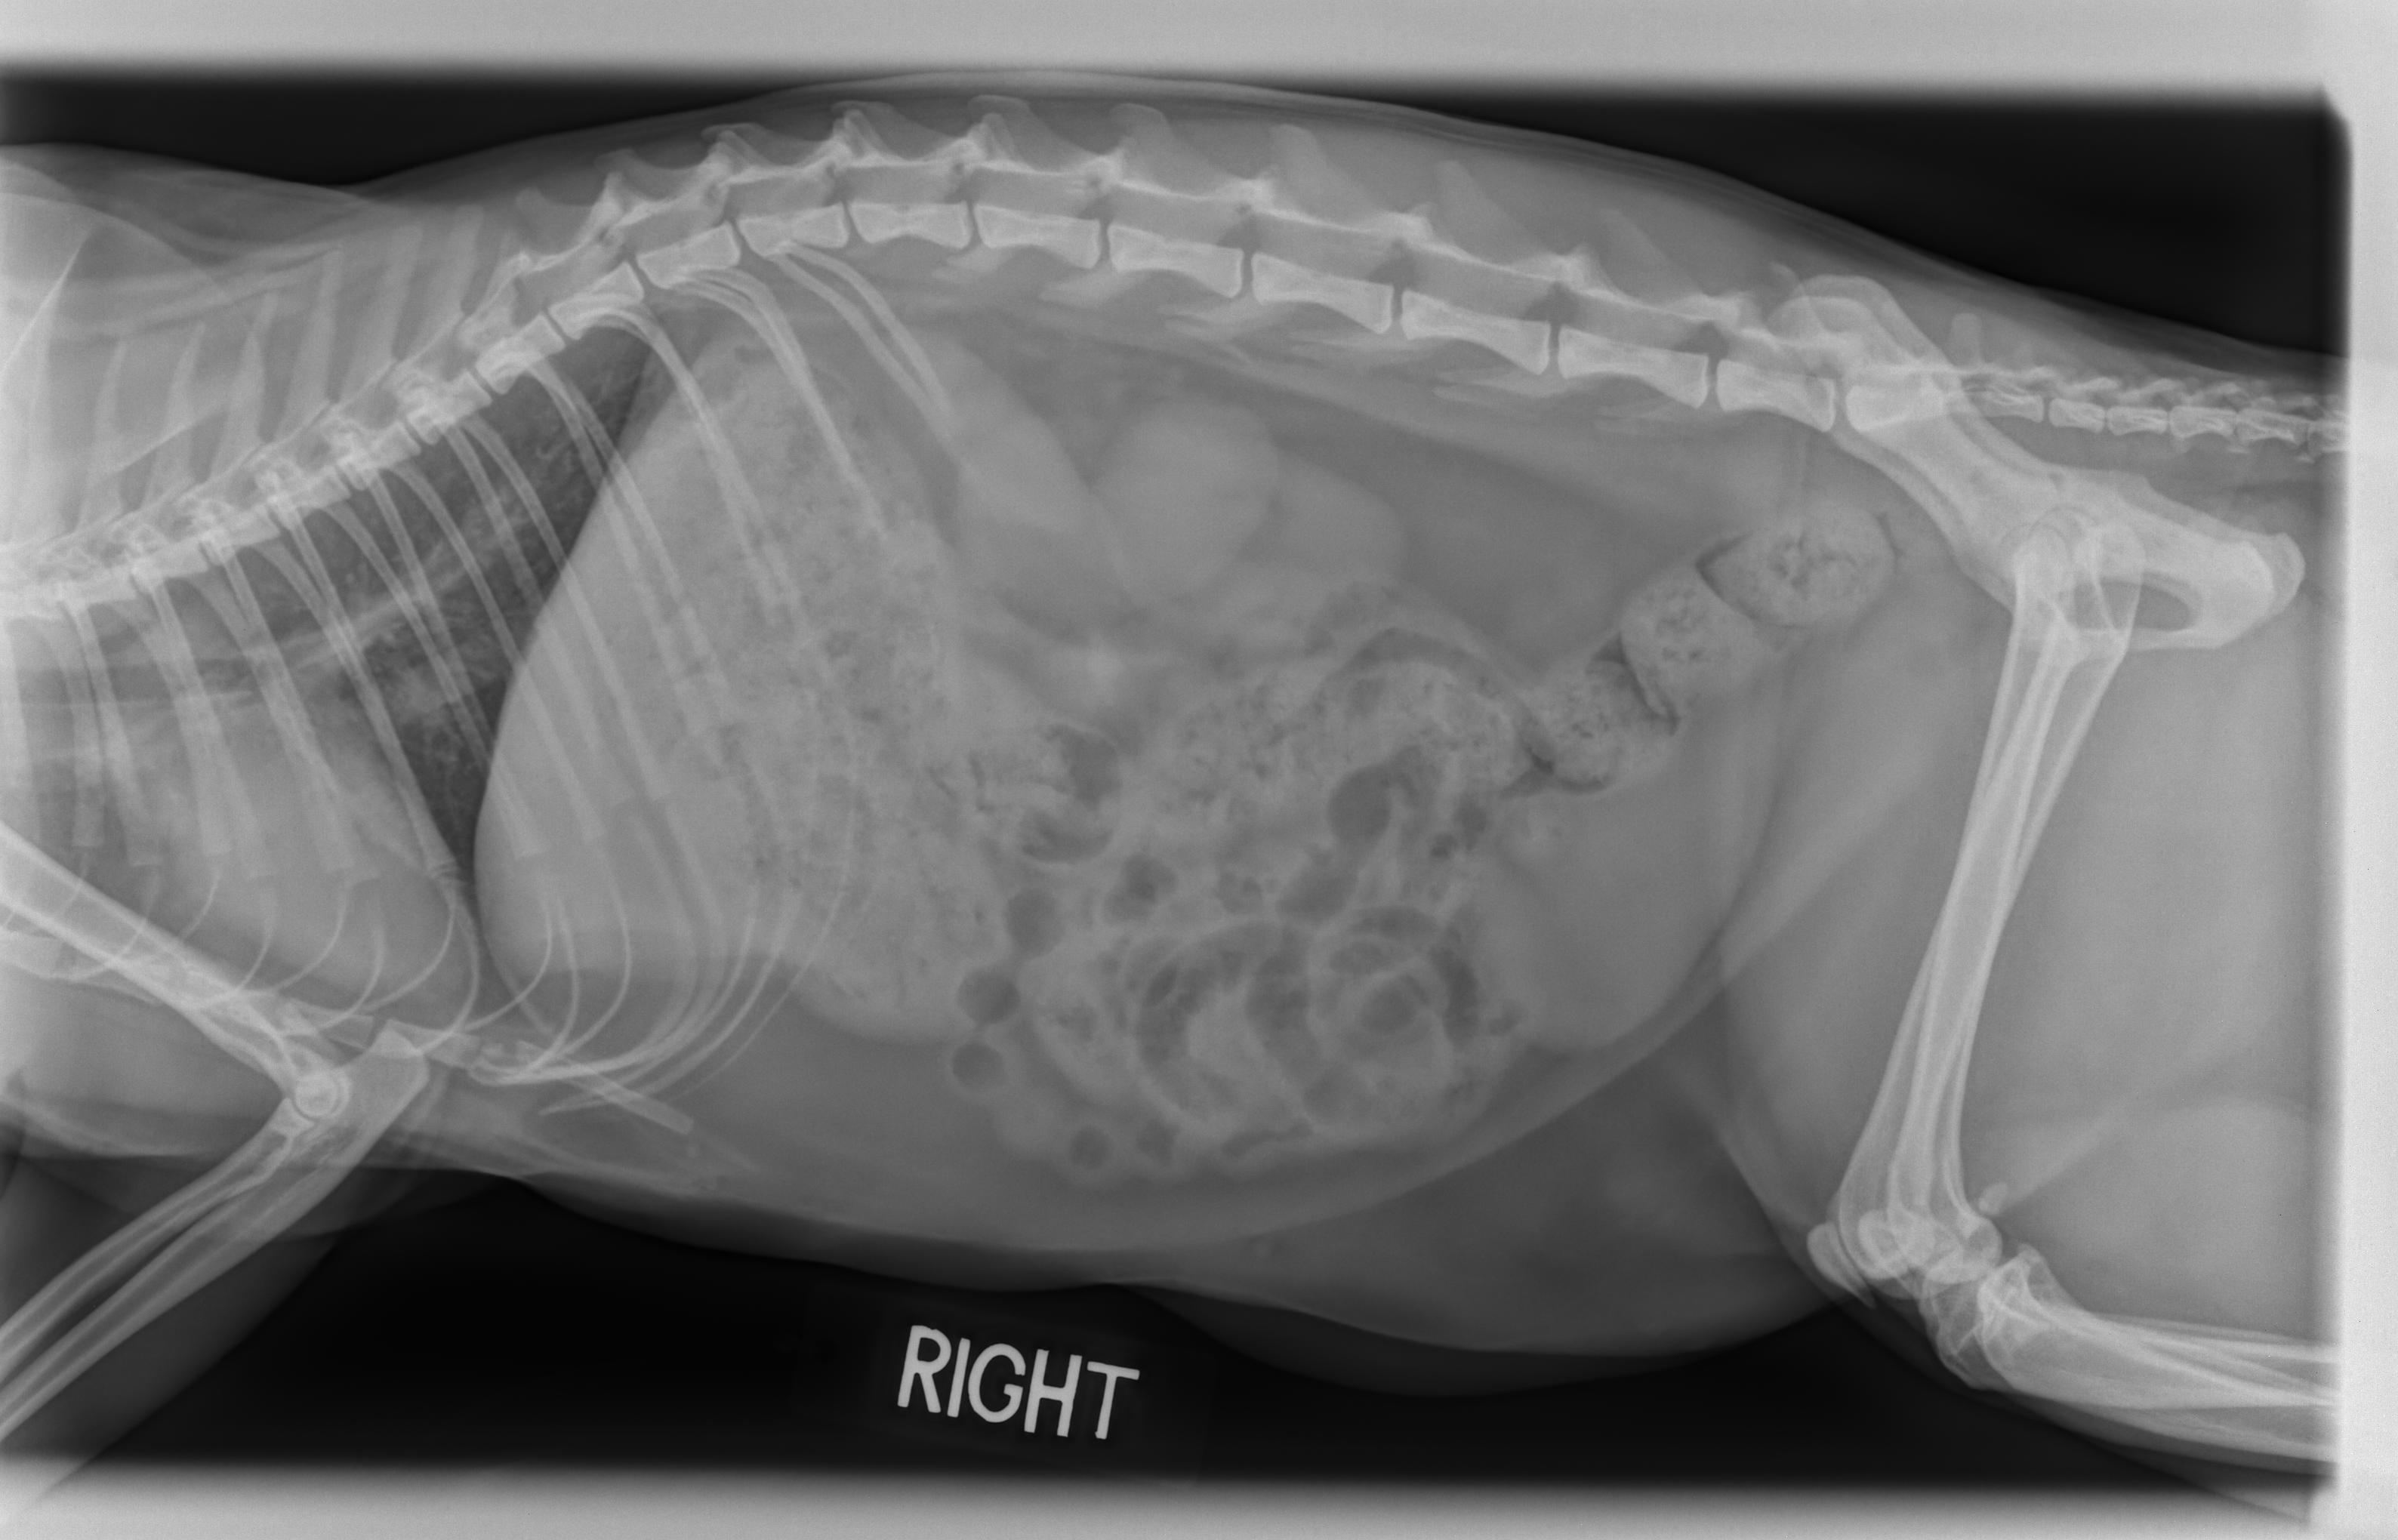

Linderman Animal Hospital utilizes digital x-rays which provide clearer and faster imaging over traditional film x-rays and can be manipulated to provide greater detailed information. This advanced technology offers us faster diagnostics with less time on the table for your pet and reduces the need for repeated exposure to radiation to capture needed views.

Radiology helps our veterinarian evaluate muscular-skeletal, cardiovascular, gastrointestinal, reproductive, and urinary systems. Our doctors realize that many issues animals may face lie just below the surface of the skin, so it is extremely important to have an advanced radiology system. Whether the problem is a simple fracture or is much more serious, our doctors and staff can get the results right away to begin the proper treatment for your pet.